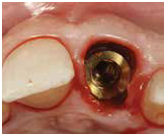

98/01/08經過三個半月做右下第一小臼齒的二階暴露,發覺鄰牙的植體高度竟已掉下來

980305幫患者補角化牙齦並翻開清除發炎組織,期待能阻止繼續骨破壞